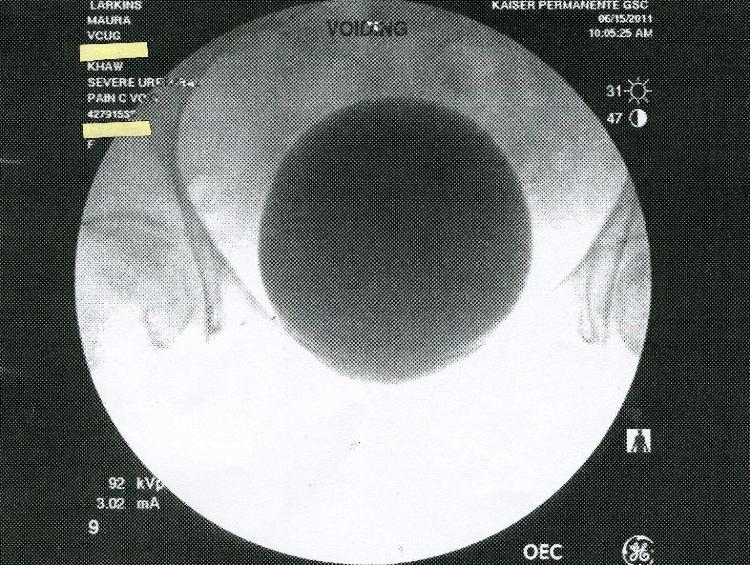

In July 2011 Kaiser Permanente in San Diego claimed that a large series of

X-rays done at the brand new Garfiled Specialty Center was not preserved on

film or saved electronically.  Kaiser claimed that only five images were

saved-on thermal paper! Below are the five images.  Incredibly, two of the

saved images are previews, or "scout" x-rays.  Why would these be printed

out?  They were not medically useful.  Answer: The truth is that all the images

were saved digitally, and Kaiser concealed them to cover-up an incorrect

diagnosis.